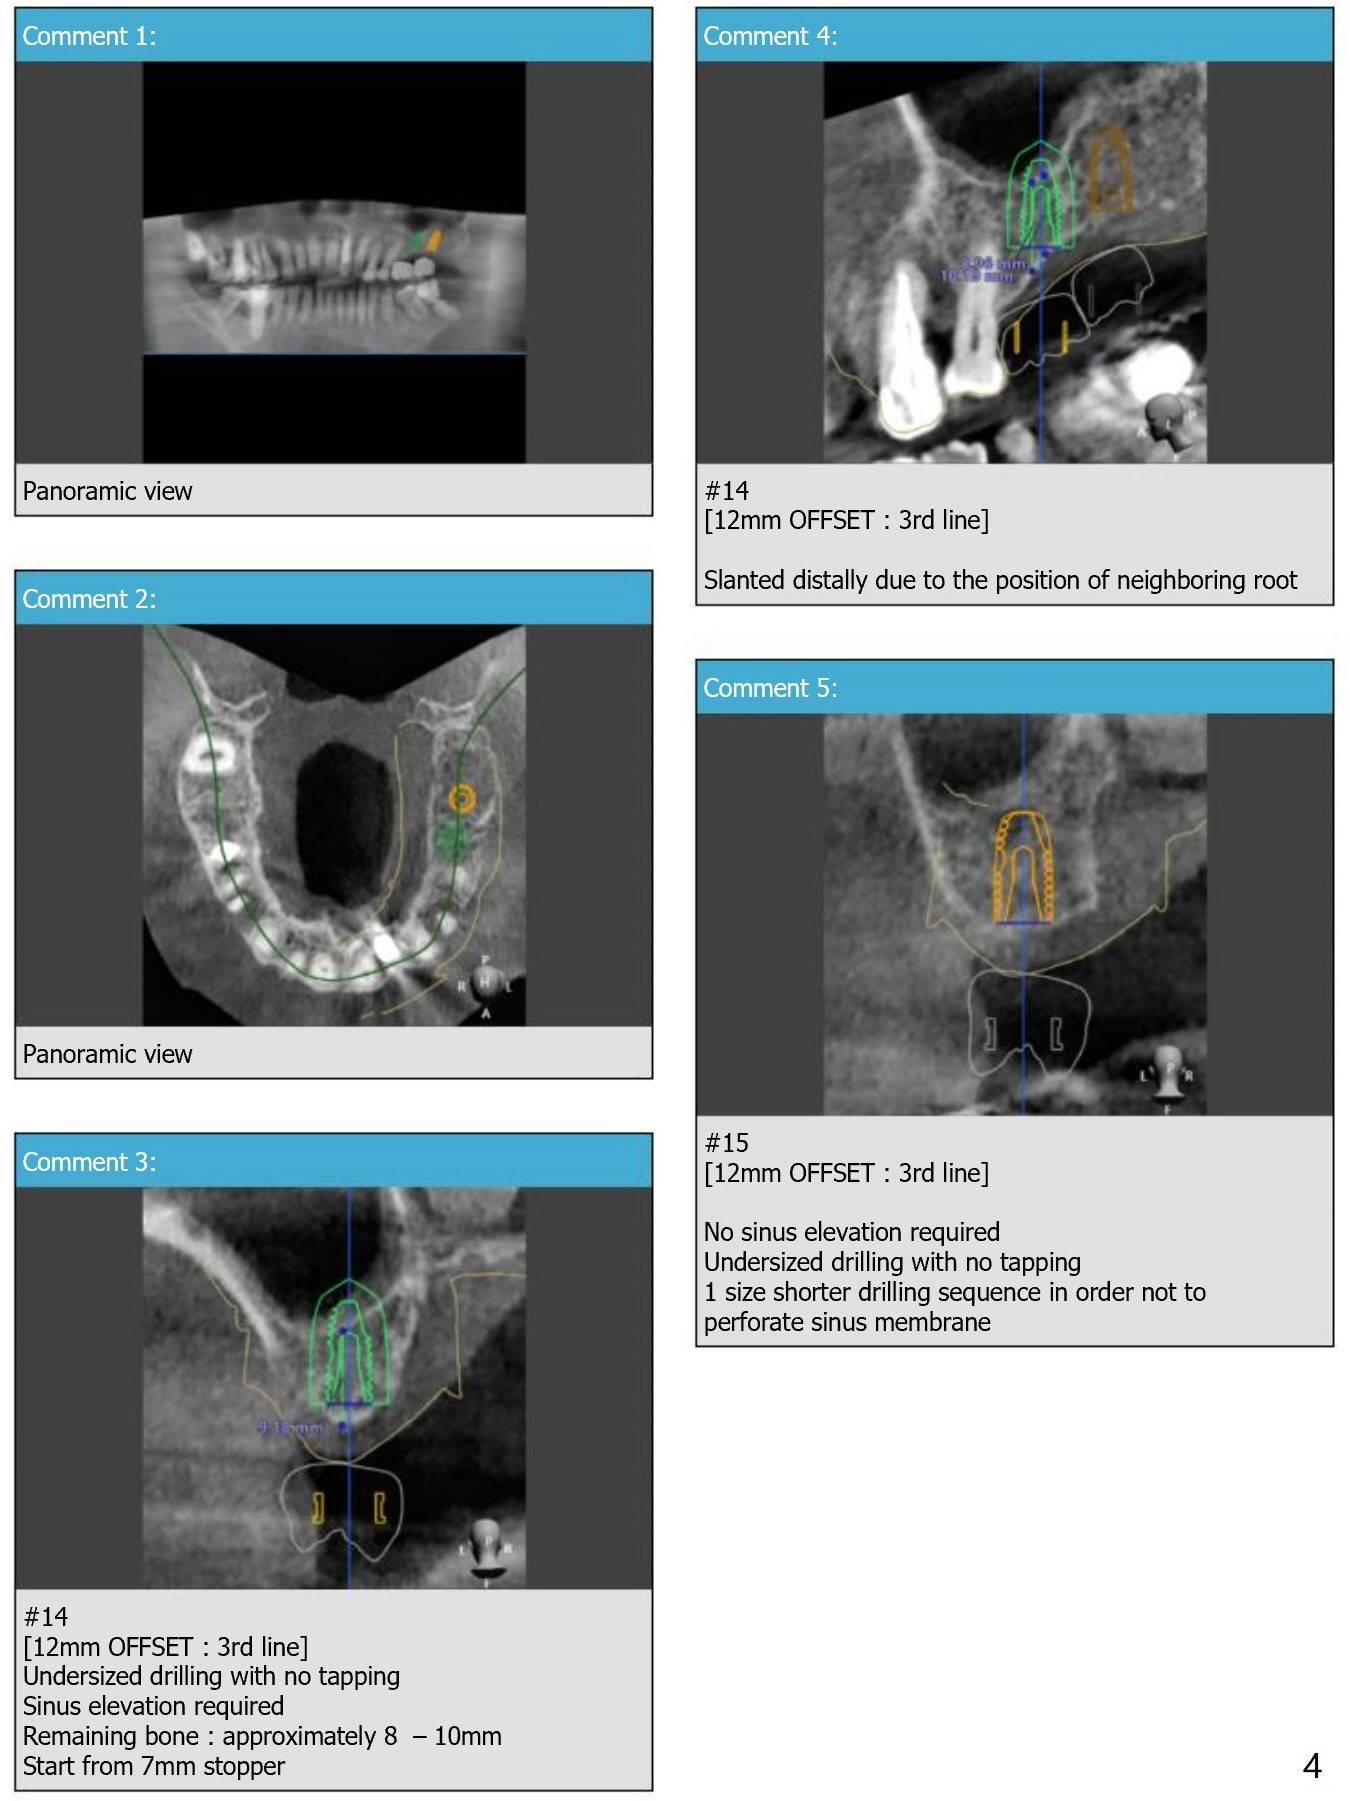

12 mm Offset

Return to Upper Molar Immediate Implant, Armaments, Close to Neighboring Curved Root

Xin Wei, DDS, PhD, MS 1st edition 04/02/2018, last revision 04/06/2018